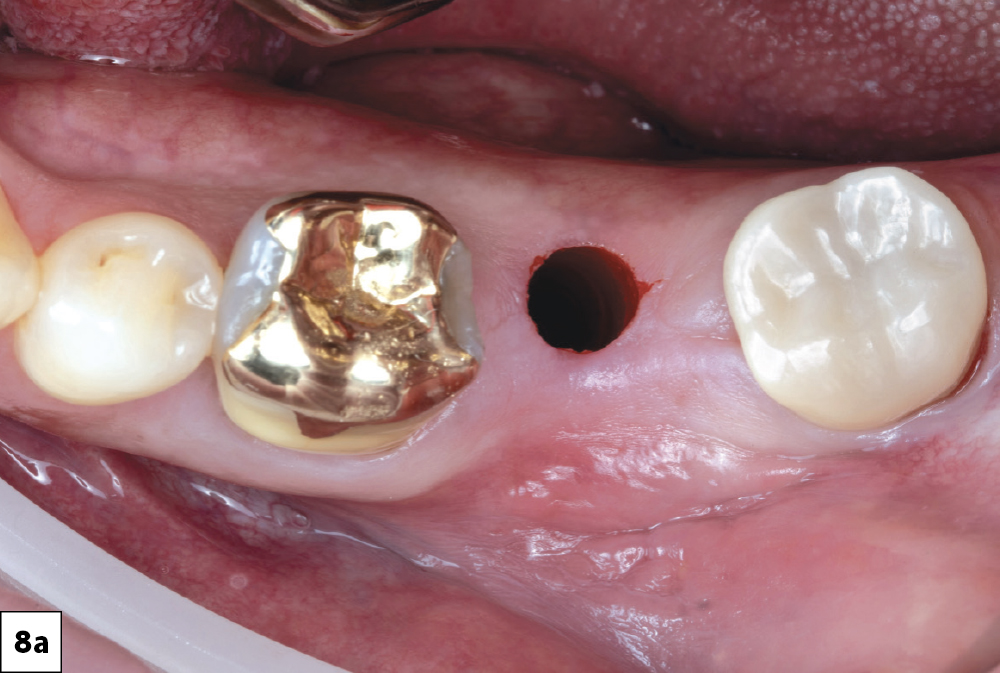

In-office milling is a quickly evolving option for the modern dental practice. With the introduction of a same-day screw-retained option, BruxZir® NOW SRC milling blocks, there’s even more opportunity for optimizing single-unit restoration workflows. In this case study, I’ll demonstrate how this product can be used as part of an efficient workflow for tooth replacement in the posterior. When combined with guided surgery and in-office crown design, this procedure offers reliable results while saving money and significantly cutting down on chair time for dentists.